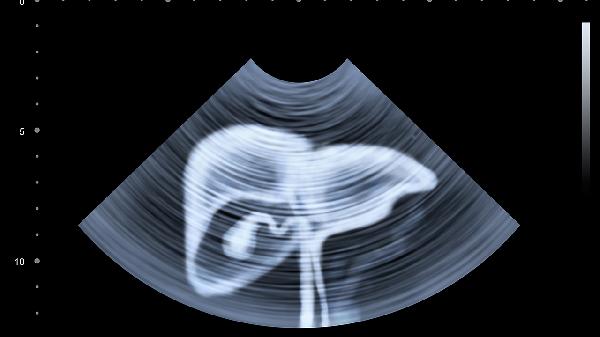

3、定期体检不能省

肝功能检查只需几十元,却能早期发现异常。有肝病家族史者建议每半年做一次甲胎蛋白检测和肝脏超声。